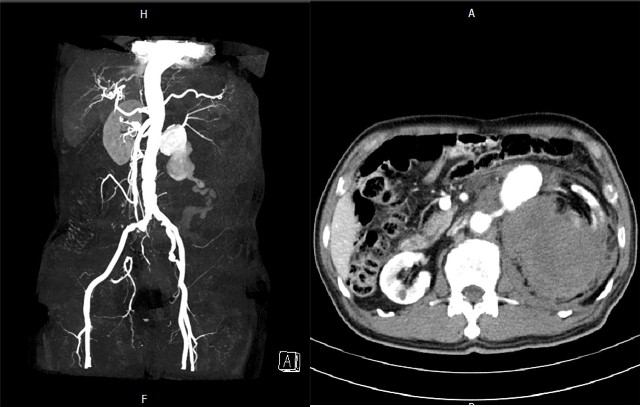

| Hình ảnh vỡ phình động mạch thận trái của người bệnh. |

Ông I. nhập viện trong tình trạng đau dữ dội mạn sườn trái, kèm theo dấu hiệu sốc và ngay lập tức được siêu âm, chụp cắt lớp vi tính bụng thì phát hiện vỡ phình động mạch thận trái.